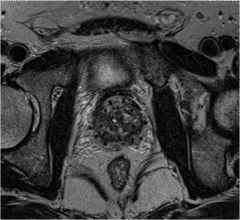

Brachytherapy is a type of radiation therapy where a sealed radiation source is placed next to or inside the area being treated. It is also important to women's health because it is a common treatment for cervical, breast, and skin cancer.